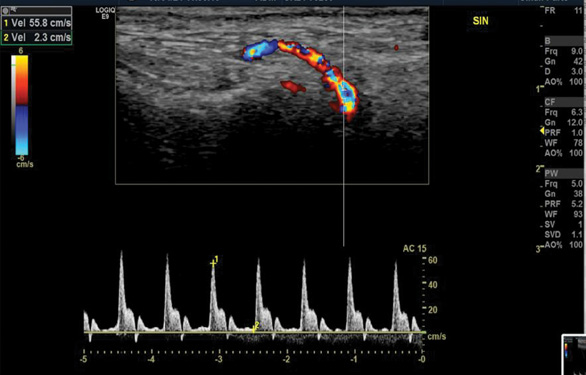

The blood test showed significantly increased CRP (208 mg/l), ESR (68 mm/h) and leucocytosis (12.30*10^9/l). Color-coded duplex sonography revealed the concentric hypoechoic thickness of the walls in both superficial temporal arteries, known as the ‘halo’ sign, which is a specific ultrasound finding in the case of GCA. The blood flow velocities of the superficial temporal artery were increased by approximately 200 cm/s bilaterally (Fig. 1 A, B).

Figure 1. Color-coded duplex sonography of the superficial temporal artery before the treatment (2019)

Color-coded duplex sonography revealed the typical ultrasound findings of temporal arteritis: the ‘halo sign’ as the dark area around the superficial temporal artery lumen probably due to arterial wall oedema (white arrows) with increased blood flow velocities on the right (A) and left (B) sides.